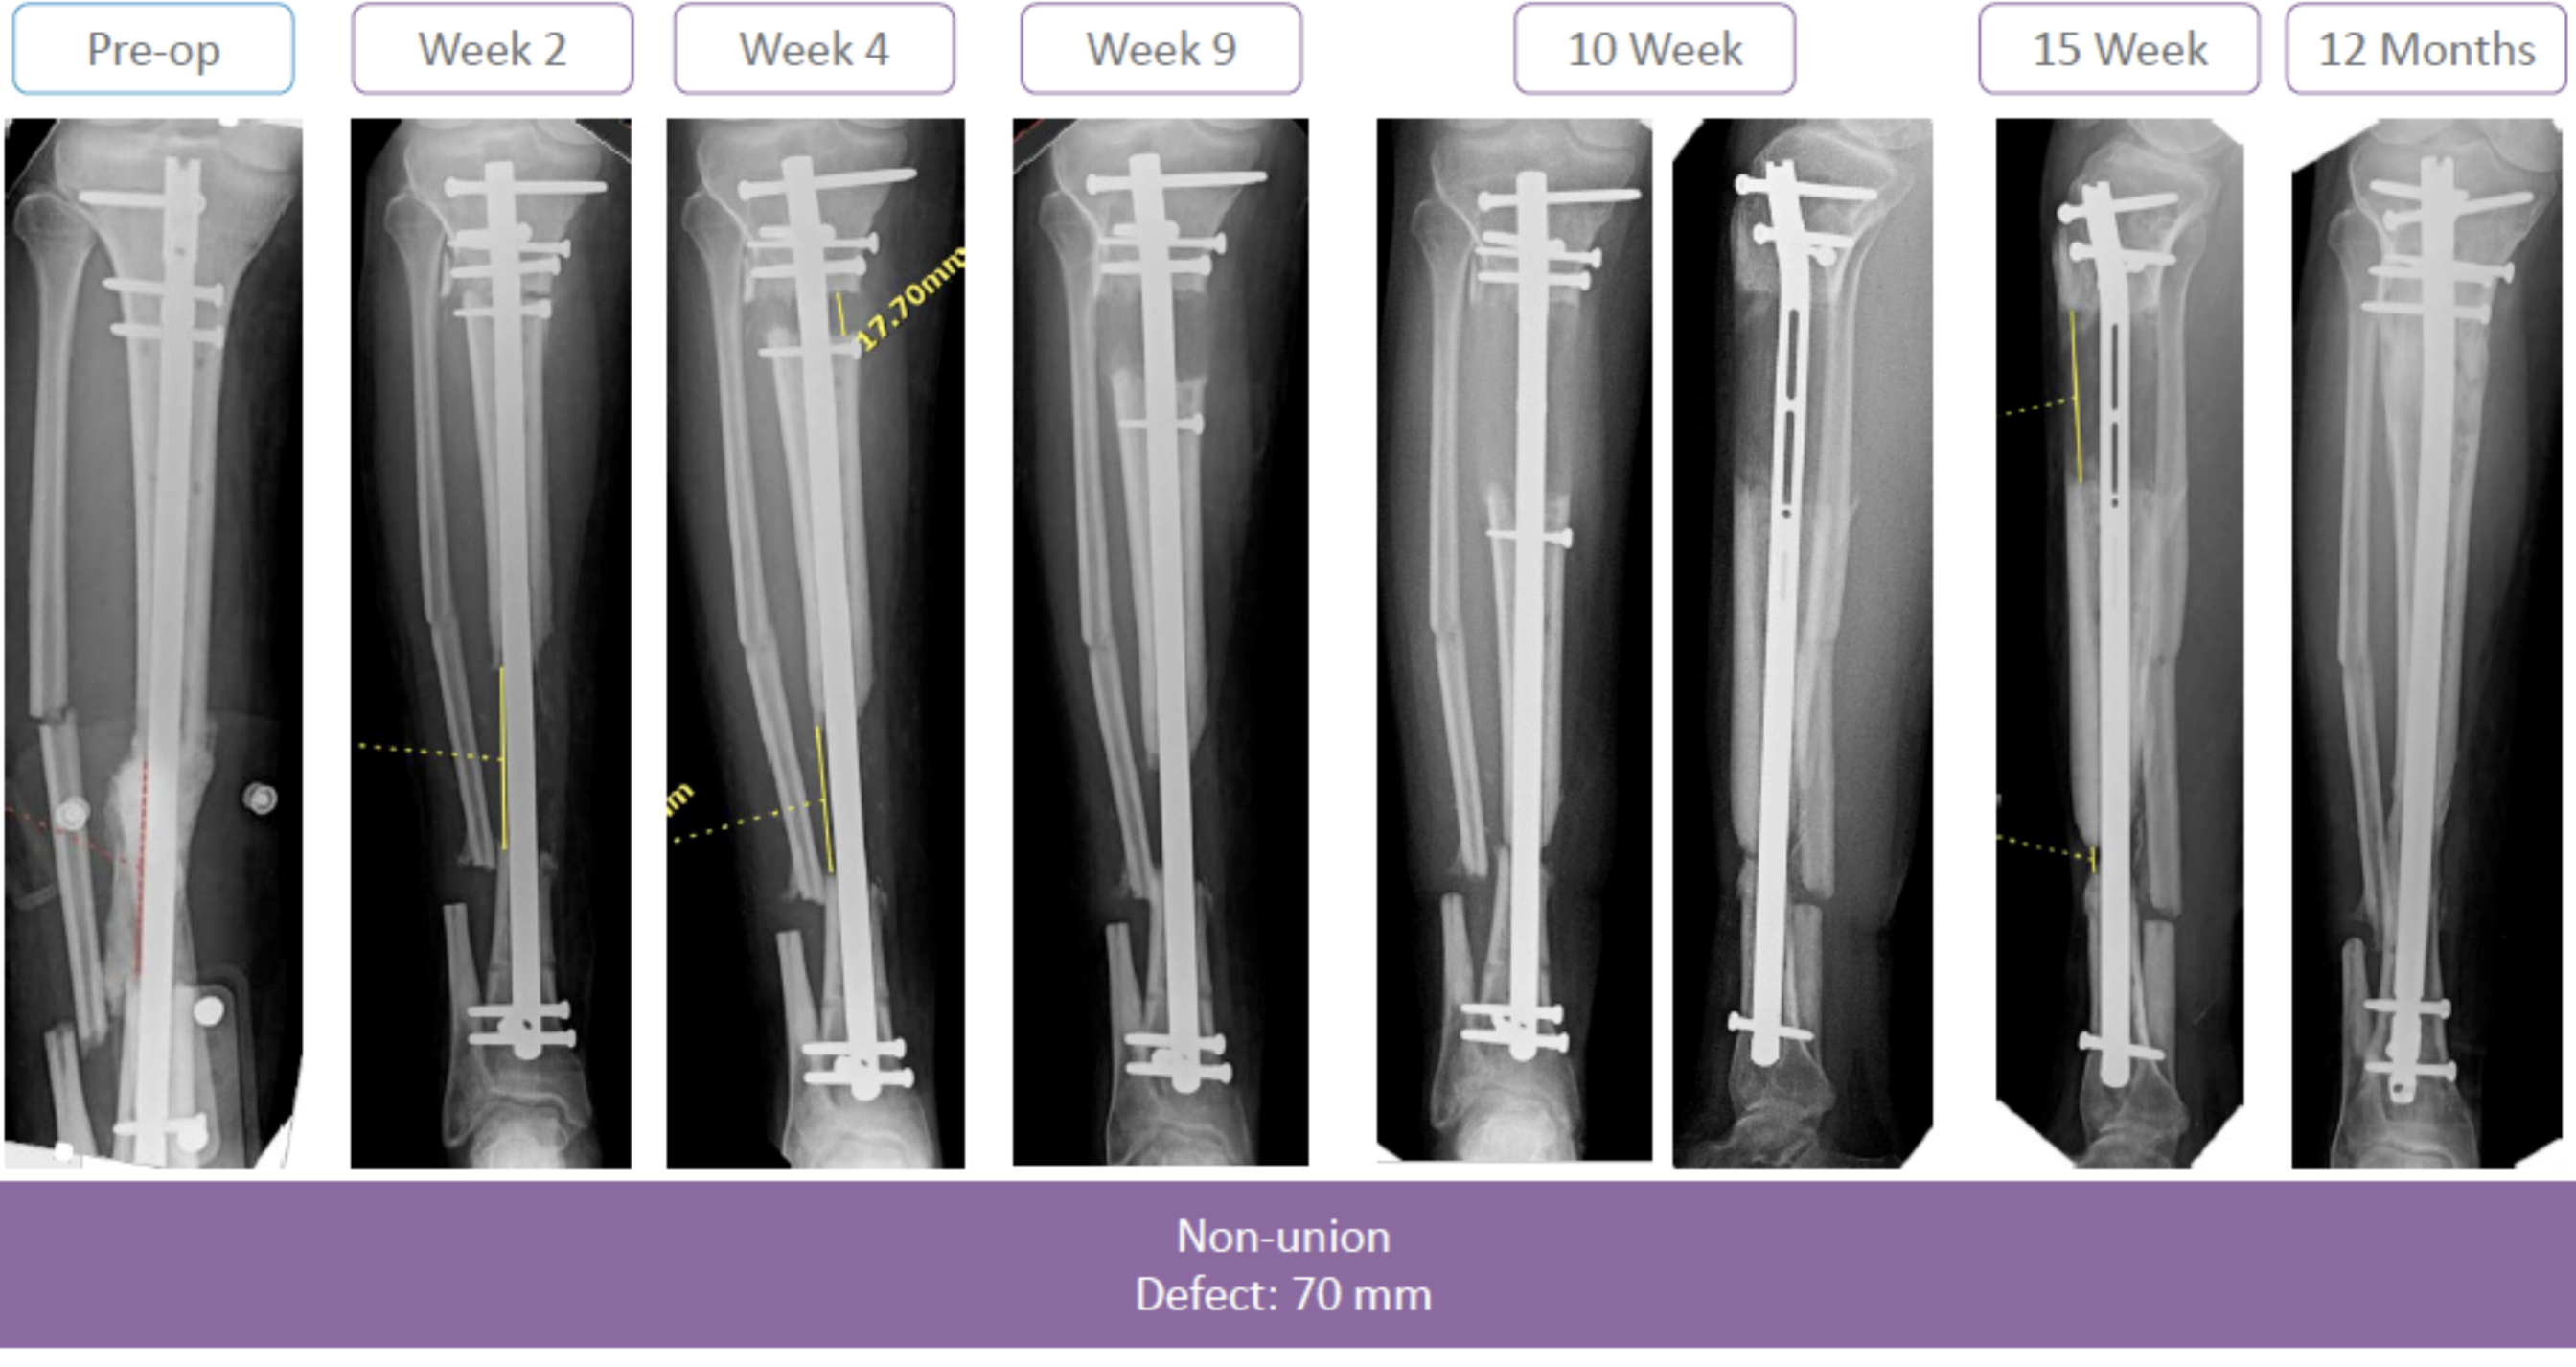

Das Precice Bone Transport System ist ein innovatives Produkt zur Behandlung von segmentalen Knochendefekten.

• Segmentale Defekte bis zu 10 cm mit einer Versorgung möglich

Das Precice Bone Transport System wurde entwickelt, um die Notwendigkeit von Externen Fixateuren bei der Behandlung von segmentalen Knochendefekten und die damit verbundenen Komplikationen zu vermeiden. Das Bone Transport System von NSO bietet einen komplett intramedullären Transport eines Knochensegments.

• Posttraumatische Defekte

• Defekte nach Resektion einer Pseudarthrose